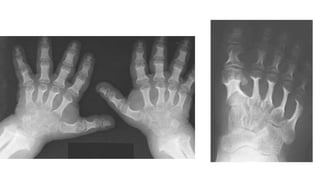

• Short and wide metacarpals and phalanges-

simulate Trident hand

• Proximal tapering of metacarpals and distal

tapering of phalanhges

• RIBS- Paddledribs(abnormally wide anteriorly) • Varus deformity of humerus, hypoplastic lateral end of clavicle, small scapula • Short and wide metacarpals and phalanges- simulate Trident hand • Proximal tapering of metacarpals and distal tapering of phalanhges

Proximal pointing of metacarpals